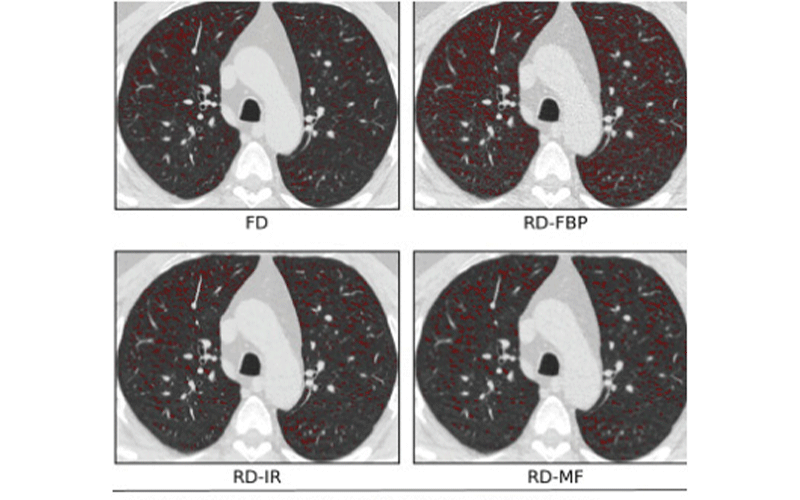

Effects of varying dose and noise reduction filtering. In this example, the difference in lung volumes between reduced-dose (RD) and standard fixed-dose (FD) scans were negligible and volume adjustment was not applied. Low-attenuating area less than −950 (LAA−950) differences between the FD, RD, RD-iterative reconstruction (RD-IR), and RD-median filter (RD-MF) scans presented in this study.

Hatt et al, Radiology: Cardiothoracic Imaging 2021 © RSNA 2021